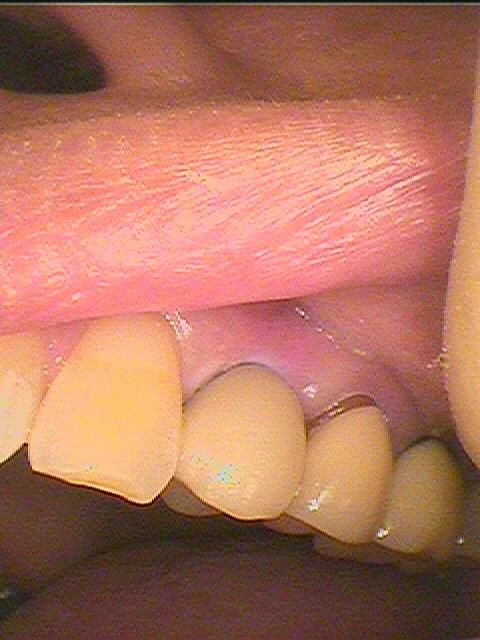

同じ方ですが、噛み合せの起点となる3,4番の歯で失活歯になると歯が割れることが多いです。| |広島市安佐南区の歯科医院 同じ方ですが、噛み合せの起点となる3,4番の歯で失活歯になると歯が割れることが多いです。 トップ お知らせ・ブログ 同じ方ですが、噛み合せの起点となる3,4番の歯で失活歯になると歯が割れることが多いです。 同じ方ですが、噛み合せの起点となる3,4番の歯で失活歯になると歯が割れることが多いです。 Web診療予約 初めての方へ 選ばれ続ける理由 院内設備について 歯が痛いしみる一般歯科 歯がぐらぐらする歯周病 健康な歯を保ちたい予防歯科 子供の虫歯予防をしたい小児歯科 銀歯をセラミックに審美歯科 白い歯を目指しませんか?ホワイトニング 矯正専門医がいるので安心矯正歯科 抜けた歯を補いたいインプラント・入れ歯 医院案内 スタッフ紹介 メリィハウス歯科クリニックオフィシャルホームページ ラベンダー歯科クリニックオフィシャルホームページ お知らせ・ブログ ホーム 診療科目 一般歯科 歯周病治療 予防治療 小児歯科 審美治療 ホワイトニング 矯正歯科 入れ歯・インプラント マウスピース矯正 初めての方へ 院長・スタッフ 設備紹介 医院案内・アクセス メニューを閉じる